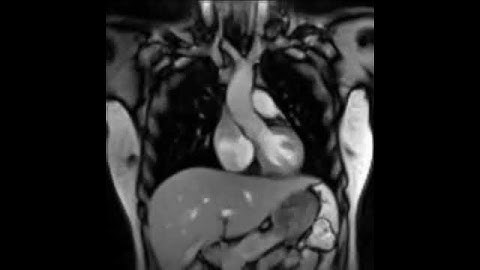

Enhancing Cardiac MRI Segmentation via Classifier-Guided Two-Stage Network and All-Slice